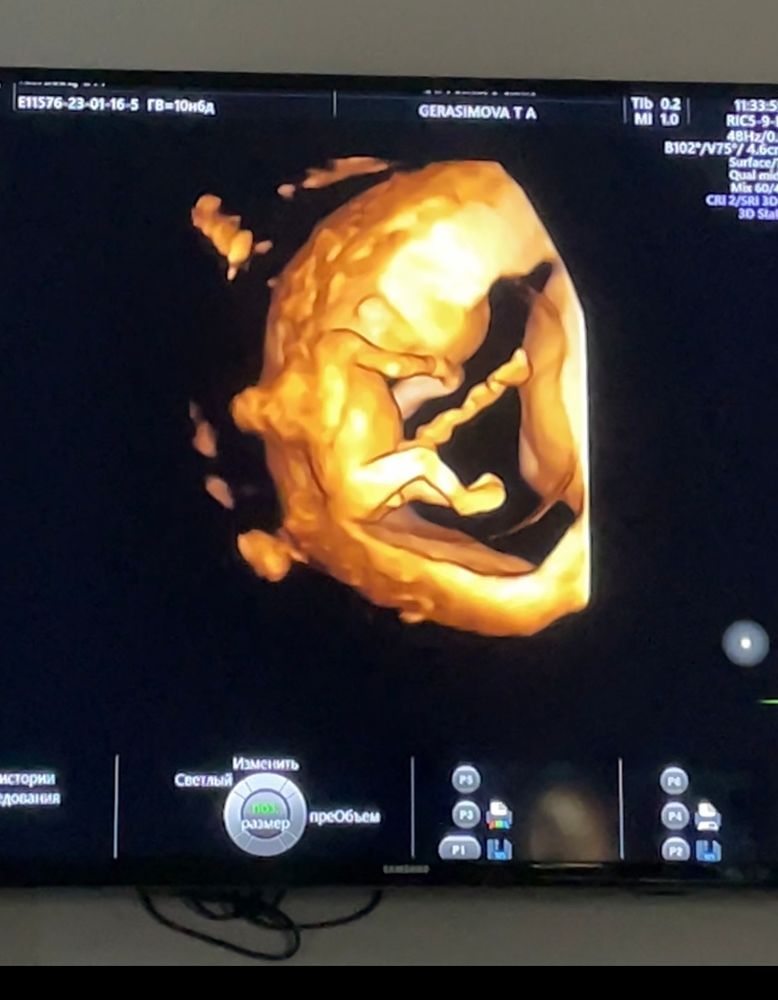

Погадаем? Мальчик или девочка?

За счет чего у вас такие выводы? То что между ног увидели бугорок? 😹 на таком сроке что у мальчика что у девочки этот бугорок есть, и там как то определяется куда смотрит этот стручок так сказать, если выше то мальчик, ниже девочка. Это можно в интернете подробнее почитать, я считаю что на девочку похоже

Вы бы до 13-14 дождались, должно быть лучше видно. На днях ходила, там врач прям со стороны попы гениталии смотрел. У вас пока на мальчика похож.

Светлана, со стороны попы тоже бугорок. Просто врач сказала, что обычно у парней побольше инструментик) на скрининг пойду через неделю-две спрошу снова.